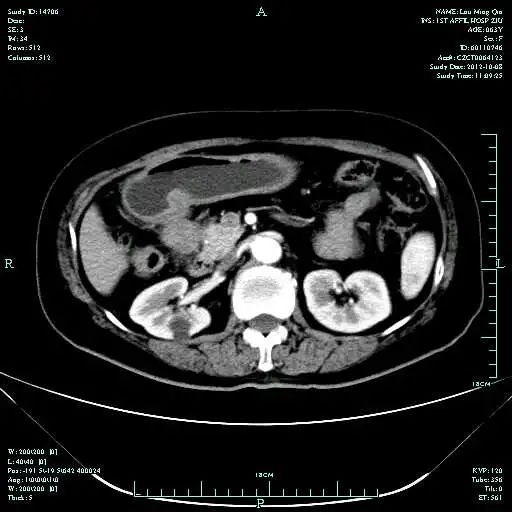

CT-T

CT-H1

影像学检查结果评估:cPD。